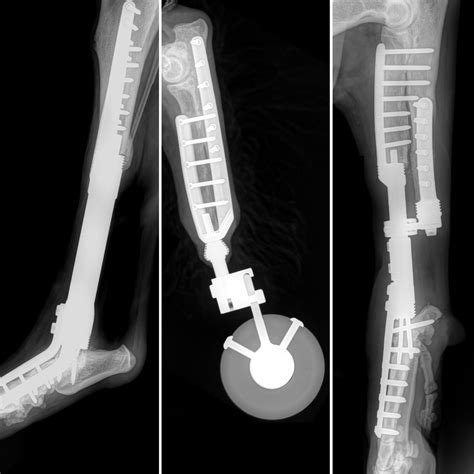

Anterior Compartment Syndrome